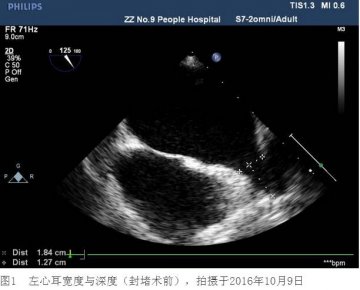

王师傅行经皮左心耳封堵术后6个月 不服用华法林了